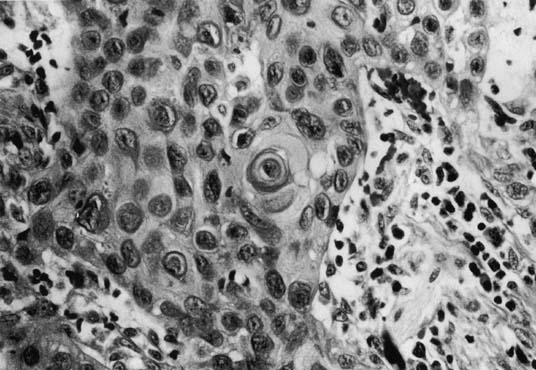

Tumor size can range from an occult lesion to a large mass measuring more than 10 cm in diameter. 35 Grossly, these tumors may be polypoid fungating masses or indurated, ulcerative plaques. On microscopic examination, the carcinoma consists of malignant squamous cells infiltrating from the vaginal epithelium and extending between the submucosa (Fig. 1). Cords of malignant cells advance into the submucosa and are usually surrounded by a large inflammatory reaction. Initially, local extension is into the submucosa, with later spread into the paracolpium and parametrium.36,37 Squamous cell carcinomas are usually moderately differentiated and nonkeratinizing. The degree of histologic differentiation, based on the amount of keratinization and number of squamous pearls, does not constitute a sound basis for assessing prognosis.24 The major prognostic factors are the stage of the tumor at the time of diagnosis and the size.16

Fig. 1. Squamous cell carcinoma of the vagina demonstrating keratin pearl formation (×200 magnification).